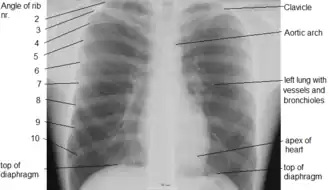

The shape of the chest does not correspond to that part of the thoracic skeleton that encloses the heart and lungs. All the breadth of the shoulders is due to the shoulder girdle, and contains the axillae and the heads of the humeri. In the middle line the suprasternal notch is seen above, while about three fingers' breadth below it a transverse ridge can be felt, which is known as the sternal angle and this marks the junction between the manubrium and body of the sternum. Level with this line the second ribs join the sternum, and when these are found the lower ribs can often be counted. At the lower part of the sternum, where the seventh or last true ribs join it, the ensiform cartilage begins, and above this there is often a depression known as the pit of the stomach.

It consists of the ribs and sternum. The ribs of the thorax are numbered in ascending order from 1–12. 11 and 12 are known as floating ribs because they have no anterior attachment point in particular the cartilage attached to the sternum, as 1 through 7 are, and therefore are termed "floating".[6] Whereas ribs 8 through 10 are termed false ribs as their costal cartilage articulates with the costal cartilage of the rib above. The thorax bones also have the main function of protecting the heart, lungs, and major blood vessels in the thorax area, such as the aorta.

The anatomy of the chest can also be described through the use of anatomical landmarks. The nipple in the male is situated in front of the fourth rib or a little below; vertically it lies a little external to a line drawn down from the middle of the clavicle; in the female it is not so constant. A little below it the lower limit of the great pectoral muscle is seen running upward and outward to the axilla; in the female this is obscured by the breast, which extends from the second to the sixth rib vertically and from the edge of the sternum to the mid-axillary line laterally. The female nipple is surrounded for half an inch by a more or less pigmented disc, the areola. The apex of a normal heart is in the fifth left intercostal space, three and a half inches from the mid-line.